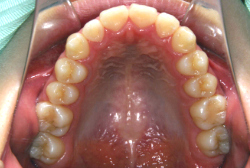

叢生(そうせい)

凸凹な歯並びのことを叢生といいます。矯正歯科に来院する患者様の主訴の中で、最も多いのが「配列の凸凹を真っ直ぐにしたい」というものです。歯の大きさと顎の大きさの調和がとれていないことが原因です。

凸凹を主体としたケースの場合、当院の平均治療期間は18ヶ月ですので、このケースは少し長めに経過しました。理由の一つは凸凹の程度がかなり重症だったと言うことですが、もう一つは、右下第2大臼歯が45度くらい前傾していたため、それを整直化させるために時間を要したと考えています。いずれにしても最終結果は大変よい状態と思います。

治療前は並びが乱れて見た目が悪いというのはもちろん問題ですが、歯科医学的に一番困るのは噛み合わせが悪いという点です。上下の犬歯(3番目の歯)は、上下的に離れた位置にあるため接触することができません。つまり歯としては存在していても、歯としては機能していないということです。